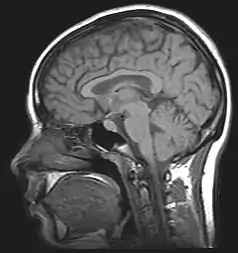

Para o diagnóstico é utilizado exames de imagem como a tomografia computadorizada, a ressonância magnética e Perimetria do Movimento para excluir a presença de tumores. Também é realizada punção lombar para manometria e exame do líquido cefalorraquidiano (LCR).